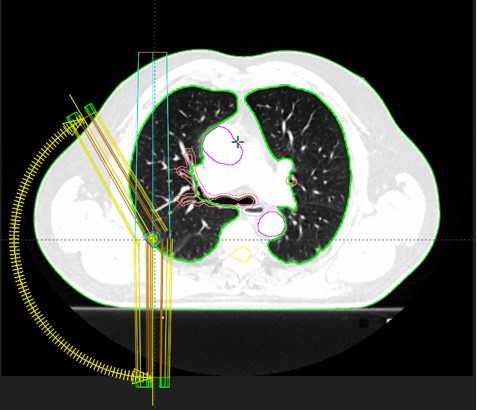

SABR meta pulmonum (08.03.-16.03.2021.; 19.08.2021.; 31.10.2022)

SABR meta hepatis, pulmonum, glandulae suprarenali lat. dex. (03.04.-13.04.2023.)

pluća 71

pluća 71 2

pluća 71 3

pluća 71 4

pluća 71 5

Rezultat – 24 mjeseca nakon RK

Potpuni nestanak tretiranih lezija